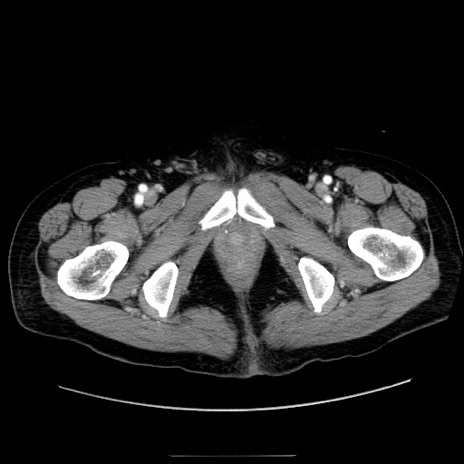

症例30(横断像)

【症例】80歳代男性

【主訴】臍周囲痛

【現病歴】約6時間前から臍下部痛が出現。次第に腹部膨隆・背部痛も生じてきたため来院。背部痛の場所は変化しない。

【既往歴】腎盂腎炎

【身体所見】意識清明、BT 36.3℃、BP  131/87mmHg、P 87bpm、SpO2 100%(RA)、臍周囲自発痛・圧痛あり、反跳痛なし、自発痛部位に一致して板状硬あり、腹部膨隆、腸雑音減弱、CVA tenderness両側陰性。

【データ】WBC 19600、CRP 0.33